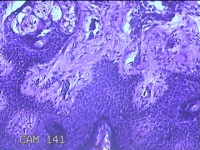

性别

男

年龄

23岁

临床诊断

右耳部肿物

一般病史

右耳前无痛性肿物20余年。

标本名称

大体所见

灰白暗红色肿物0.7x1.5x0.2cm一个,表面糜烂。

组织没固定好